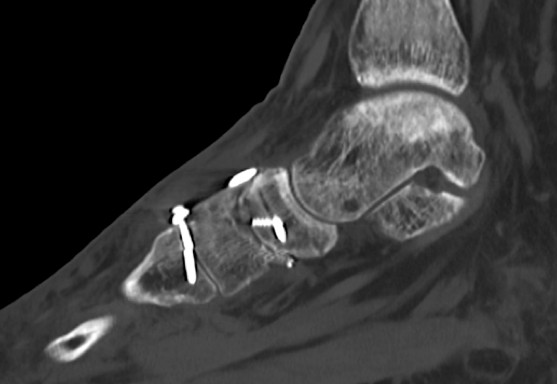

Im CT vom September 2017 ergab sich noch kein Durchbau der Arthrodesen, aber ein Bruch der das TMT 2 überbrückenden Schraube.

6.- 09/2017 Schraubenbruch

Durch die Fehlplatzierung der Plattenschraube ist es zu einem erwarteten Schraubenbruch in Höhe des 2.Mittelfußgelenkes gekommen. Die abgebrochene Schraube überragt die Gelenkfläche des 2.Mittelfußstrahls und führt dort zu einer mechanischen Irritation mit zwingend nachfolgender Verschleißerkrankung, die aus dem Vergleich der CT Aufnahmen von 19.04.2018 und September 2017 bereits deutlich zu erkennen ist.